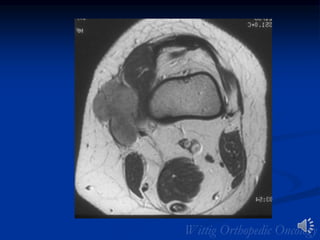

Leiomyosarcoma

• 9% of all soft tissue sarcomas

• Age: Median age 40 to 60 years

• Sites:

• Retroperitoneum—Most common

• Thigh—Second most common

• 6% of subcutaneous sarcomas

• May arise from wall of blood vessel

• Clinical: Painless mass

• Radiology: Non specific heterogeneous mass with necrosis

and hemorrhage

• Remainder of lesions in GU and GI tracts

• 5th and 6th decades

• Metastases common

• Imaging similar to MFH/fibrosarcoma

• Extremity lesions usually intramuscular

• Central necrosis/hemorrhage common

• Calcification/osseous invasion rare